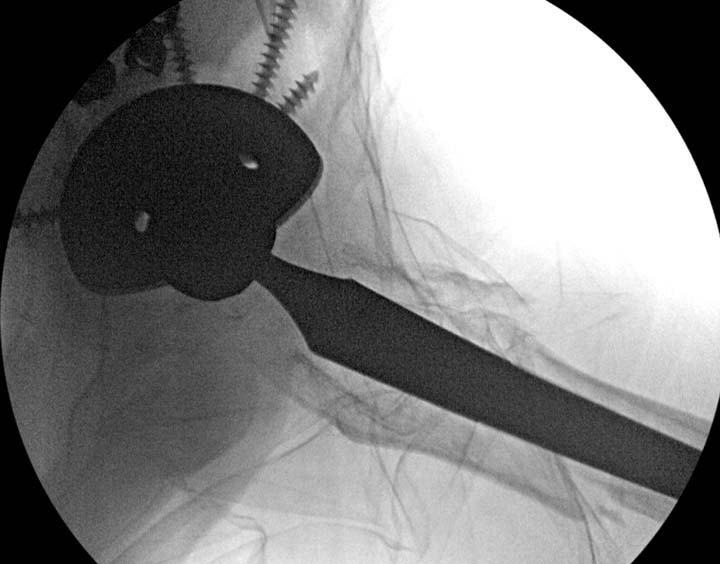

остаться до конца лечения, начал изучать язык... Для облегчения

транспортировки на второй день после поступления правая сторона была

фиксирована ретроградным гвоздем.

Теперь по серьезному. Учитывая качество кости и низкий гемоглобин,

периодический гемодиализ и воодушевленный результатом выступлении

Челнокова, вместо пластины решил попробовать гвоздь. Но жесткие FDА

условии не позволяют воспользоваться дивайсом до получения разрешения на

пользование.

Гвоздь из ретроградного гвоздя DePuy в 15 мм получился немного тоньше,

чем у Российских коллег.

Операция не обошлась без казуса, при подготовке гвоздя произошла ошибка

в расчете. Пришлось коррегигировать по ходу операции, где длинный

дистальный отдел гвоздя срезали во время операции.

А так вроде первый американский опыт прошел удачно. У больного низкий

гемоглобин, который подправили во время операции переливанием крови.

надеюсь, контрагированные мышцы сохранит длину конечности. Контрольный

снимок показал устойчивую фиксацию.